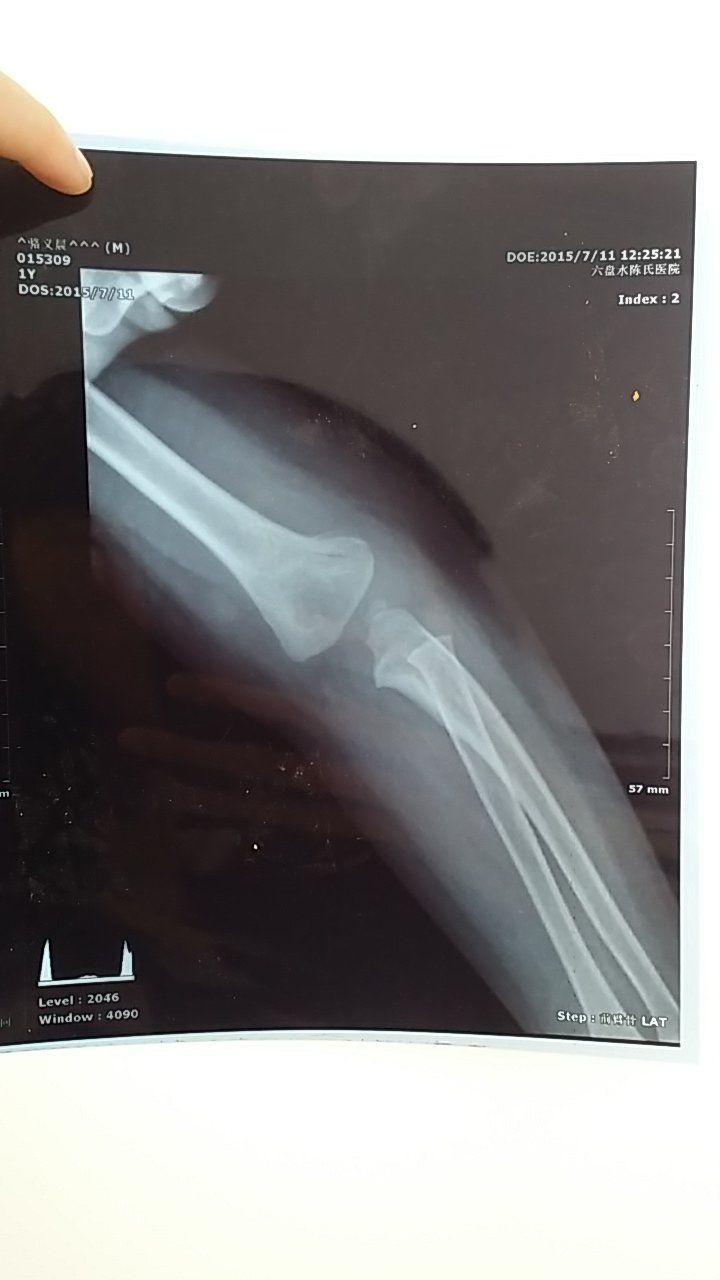

宝宝一岁半 手肘摔骨折 医生说两周就可以拆石膏 现在打石膏第五天 可以抬手臂手指拿东西灵活是不是 宝宝一岁半 手肘摔骨折 医生说两周就可以拆石膏 现在打石膏第五天 可以抬手臂手指拿东西灵活是不是证明恢复得不错 轻轻碰触骨折处也没有疼痛感 点击展开 匿名用户 2015-07-16 16:53 为您推荐: 其他回答 这可能跟你们大人抱宝宝的方法有关系,以后注意点。。。 匿名用户 2015-07-16 17:06 毕竟还小、 匿名用户 2015-07-16 17:02 还是要多注意 匿名用户 2015-07-16 17:02 最好少动动吧, 防止骨头长不好 匿名用户 2015-07-16 16:57 相关问题 小孩趾骨骨折打上石膏石膏,手指是不是得运动 两岁宝宝手臂骨折后手指肿胀了四五天,三月后手指甲脱落长新的正常吗? 宝宝手臂骨折后手指肿胀了四五天,三月后手指甲脱落长新的正常吗?